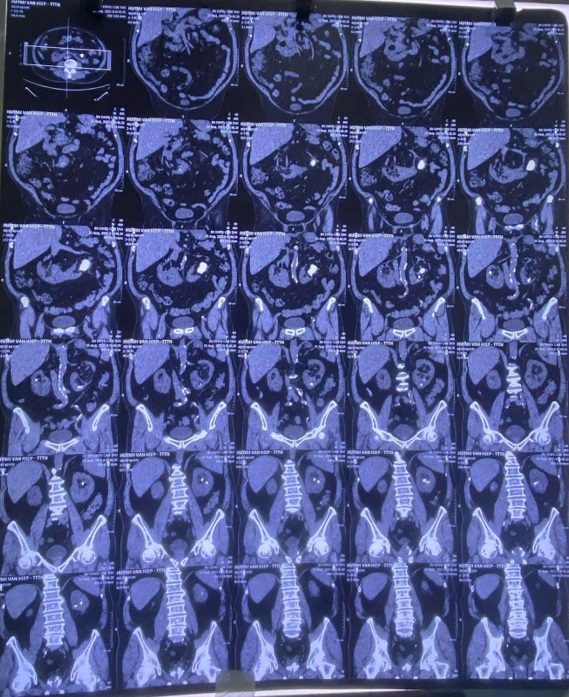

Qua thăm khám và chẩn đoán hình ảnh, các bác sĩ xác định bệnh nhân bị sỏi san hô thận trái và sỏi nhỏ thận phải trên nền thận dị dạng bẩm sinh – gọi là thận móng ngựa. Đây là tình huống phức tạp vì thận móng ngựa có cấu trúc giải phẫu khác thường, khiến việc phẫu thuật lấy sỏi khó khăn hơn nhiều so với bệnh nhân thận bình thường.

Sau khi hội chẩn, bệnh nhân được chỉ định lấy sỏi thận qua da bằng đường hầm nhỏ (mini-PCNL) đối với sỏi san hô ở thận trái. Kíp phẫu thuật gồm ThS.BS Đặng Hoàng Minh, ThS.BS Lê Thanh Bình, ThS.BS Dương Văn Huynh và BS Tô Ngọc Đăng Khoa. Ca mổ kéo dài khoảng 3 tiếng với nhiều thử thách nhưng đã diễn ra thuận lợi.

Kết quả: sỏi được lấy sạch, thận được bảo tồn tối đa, tổn thương mô xung quanh rất ít. Bệnh nhân hồi phục nhanh, xuất viện sau 3 ngày và tái khám 2 tuần sau hoàn toàn sạch sỏi, đã được rút ống thông.